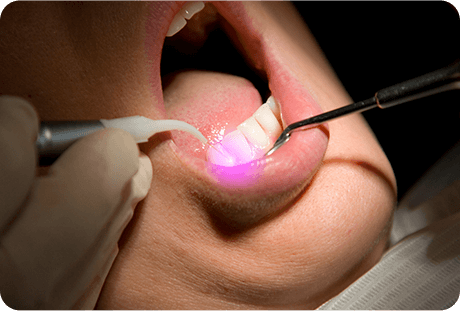

当院では「アーウィンアドベールEVO」を導入し、保険診療にてう蝕、切開、口内炎治療等のレーザー治療が可能になりました。

歯ぐきの黒ずみにレーザーを照射することで、メラニン色素を除去し、明るいお色味の歯ぐきを取り戻すことができます。当院では痛みと振動が少なく、身体にもやさしいレーザー「アーウィンアドベールEVO」で施術を行います。